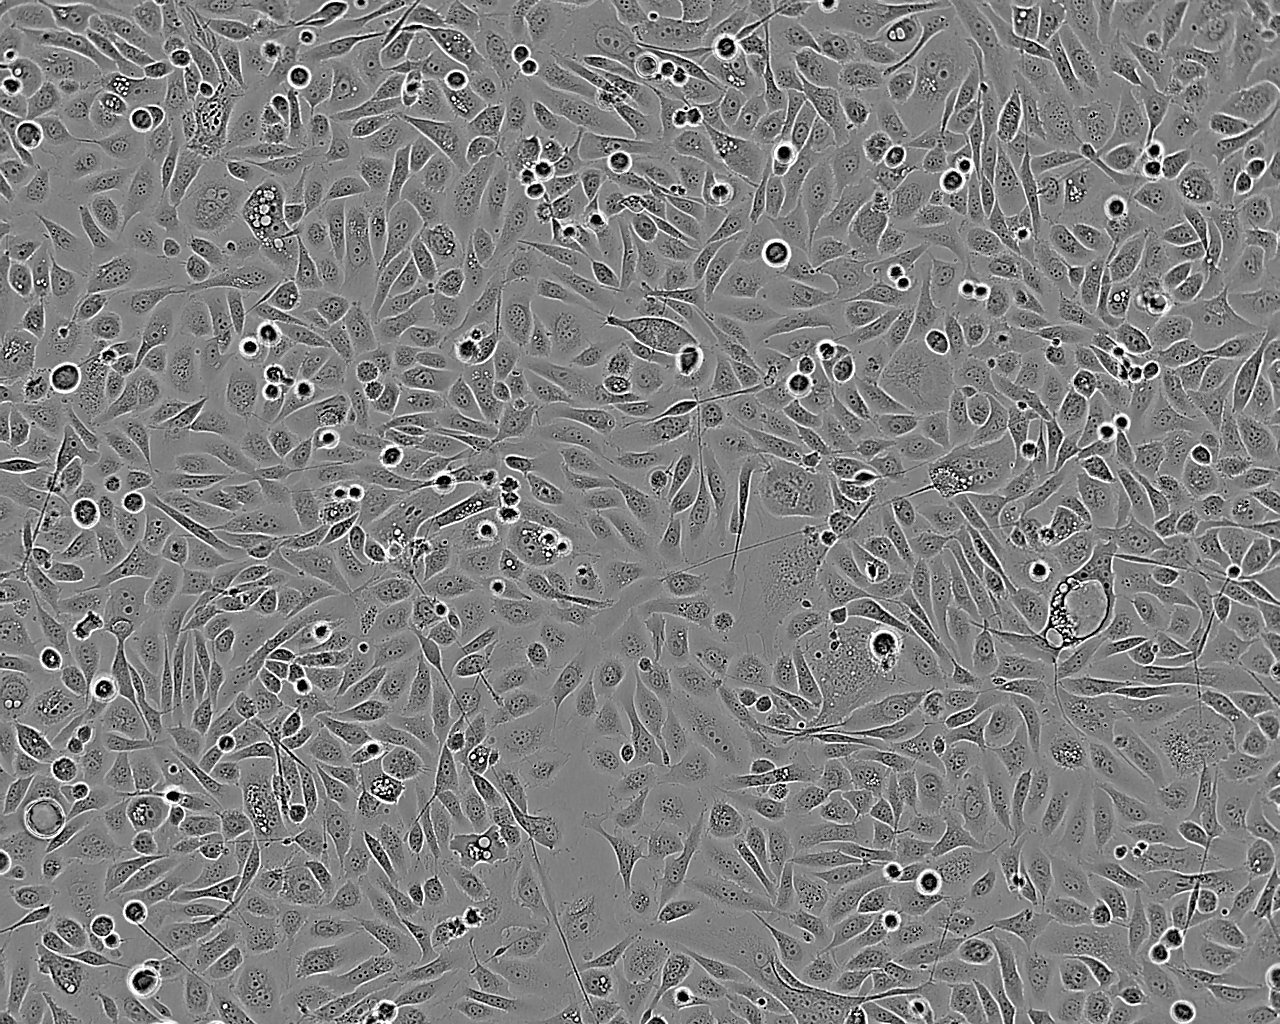

PC-3

Established from a grade 4 prostatic adenocarcinoma from a 62 year old male Caucasian. The cells grow in agar and produce tumours in nude mice. Exhibit low acid phosphatase and testosterone-5-alpha reductase activity. The Y chromosome could not be detected in this cell line by short tandem repeat (STR)-PCR analysis when tested at ECACC. It is a known phenomenon that due to the increased genetic instability of cancer cell lines the Y chromosome can be rearranged or lost resulting in lack of detection. The cell line is identical to the source provided by the depositor based on the STR-PCR analysis.

Epithelial

Split sub-confluent cultures (70-80%) 1:2 to 1:6 i.e. seeding at 2-5x10,000 cells/cm² using 0.05% trypsin/EDTA; 5% CO₂; 37°C. Medium change every 5 days. The initial subculture interval after cells are thawed may be longer than 7-9 days.

Adherent